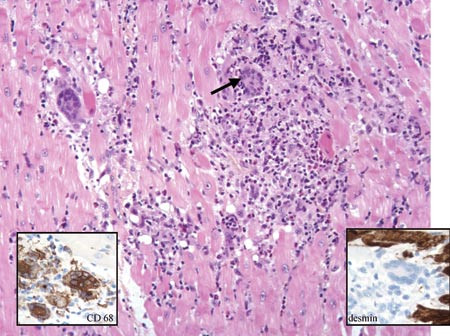

Det ble startet behandling med intravenøst amiodaron. Da pasienten forble hypotensiv og stadig ble dårligere, ble han lagt i respirator, fikk aortaballongpumpe og etter hvert behandling med ekstrakorporal membranoksygenering. Det ble utført perkutan endomyokardbiopsi fra høyre ventrikkel, og samtlige fem biter viste forandringer typisk for kjempecellemyokarditt (fig 1). I tillegg til hjertesviktbehandling ble det startet med immunsuppressiv behandling i form av ciklosporin, prednisolon og anti-T-lymfocyttglobulin (OKT3). Gradvis stabiliserte hjerterytmen seg. Samtidig var det bedring av pumpefunksjonen, slik at de understøttende pumper kunne fjernes etter ca. en uke. Det ble implantert defibrillator som profylakse mot fatal arytmi. Ved utskrivning fortsatte man med immunsuppresjonsbehandling i form av ciklosporin og prednisolon.

Makroskopisk ses i aktiv fase konfluerende områder med nekrose som affiserer både høyre og venstre ventrikkel. Mikroskopisk ses i det akutte stadium nekrose av myocytter med infiltrasjon av lymfocytter, makrofager, flerkjernede kjempeceller av langerhanstype og oftest eosinofile granulocytter. Kjempecellene er immunfenotypisk makrofager (fig 1), i hvert fall i tidlige faser av sykdommen (7). Senere, på reparasjonsstadiet, kan kjempeceller av myogen opprinnelse ses, disse har annen immunfenotype. Fulminante tilfeller viser utbredte lesjoner, mens i tilfeller med mer indolent forløp kan det være fokale lesjoner og store områder med helt uaffisert muskulatur. I senere stadium er det færre kjempeceller og begynnende fibrose. I tilhelet fase see fokal fibrose, ofte uten betennelse.